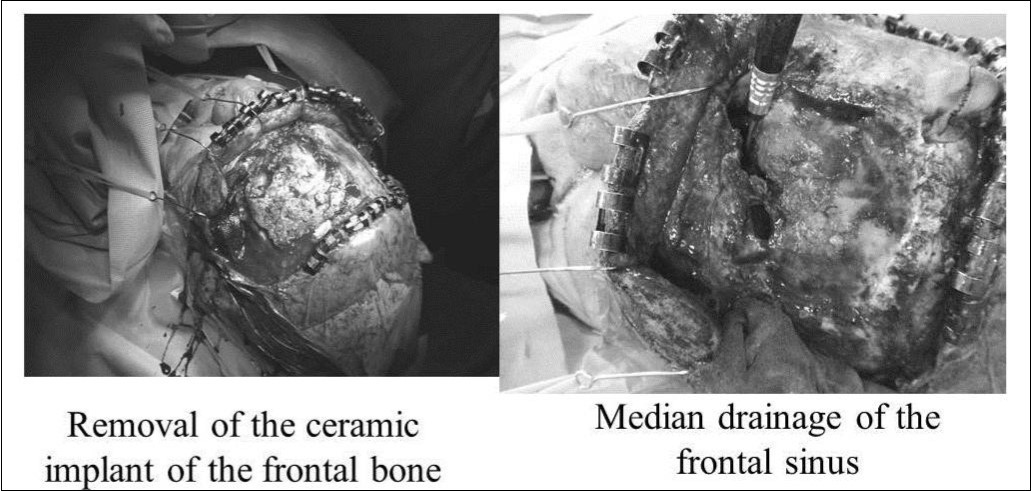

On April 28, 2007, craniotomy was performed under general anesthesia, with removal of the ceramic implant and median drainage of the frontal sinus (Figure 2). Two cysts in the left lateral frontal sinus were opened. One cyst was inflamed with thickened mucosa. The left and right frontal sinuses were opened widely, the anterosuperior nasal septum was excised, and a large drain was placed (Figure 3). A new ceramic implant was not placed because of infection and contamination. The operative time was 4 h 25 min (surgery completed at 18:30). Blood loss was 400 mL, without the need for any transfusions. During endotracheal intubation and extubation, no significant changes in blood pressure were observed, nor were any arrhythmias identified. During surgery, epinephrine gauze (1:5000) was used several times, and a total of 15 mL of epinephrine (1:20,0000) was injected intranasally. Specifically, no intraoperative manipulation or compression of the left eye was performed. Just before completion of surgery, gauze with Achromycin ointment was packed into the nasal cavity, the absence of bleeding was confirmed, and surgery was completed.

Figure 2.Craniotomy and median drainage. Left: Removal of the ceramic implant from the frontal bone. Right: Median drainage of the frontal sinus.